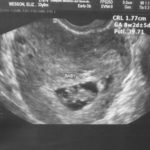

Pregnancy

Our story 2